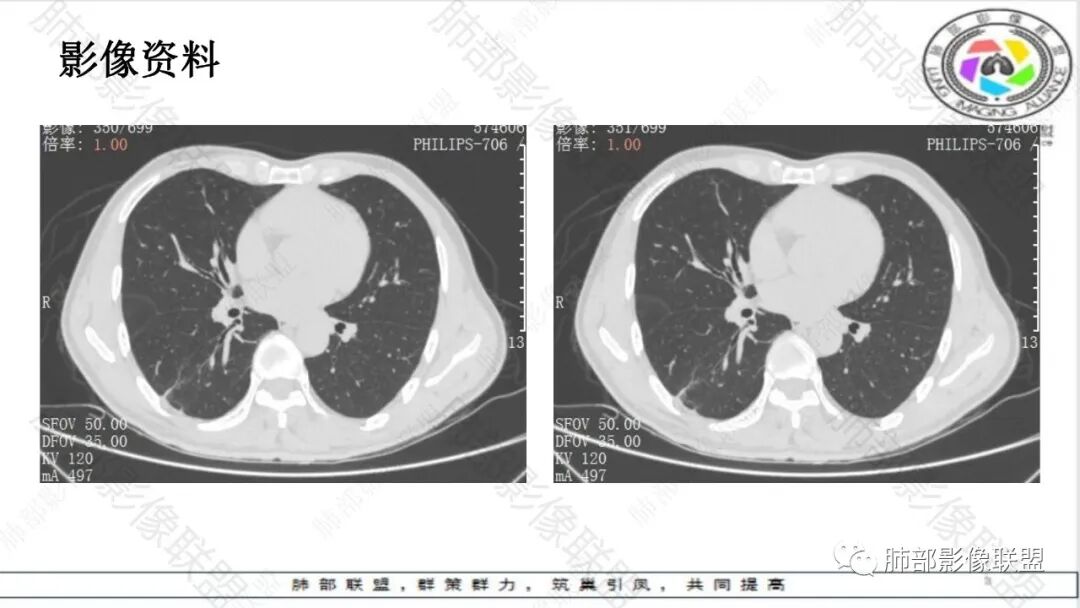

1.病例特点:中老年男性,长期睡眠异常(嗜睡),焦虑状态。病例右肺下叶长条片状病灶,实性密度为主,轻度强化,边缘多平直(可见尖角征),未见明显膨隆分叶及毛刺,边缘见模糊磨玻璃影,未见钙化、液化或空洞。病灶长轴顺延下叶支气管方向,长索条状牵张于胸壁肺门间,轻度胸膜凹陷。病灶内见支气管、血管通行,气管略壁厚。

未见卫星病灶,未见“树芽征”或拐枣样改变“拐枣征”。未显示新旧不等改变。

右肺门及纵膈未见肿大淋巴结。

2.综合分析:条片状病灶,边缘平直,尖角,未见典型的分叶毛刺,少张力,也未见边界清楚的磨玻璃晕,同侧肺门及纵隔未见增大淋巴结等等,总之,如多数老师分析,缺乏典型恶性肿瘤影像学特征。

病灶相对孤立,未见钙化或新旧不等,未见“树芽征”或“拐枣征”,亦未见典型继发性肺结核影像学特点。